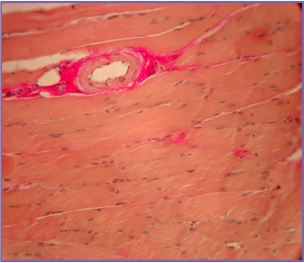

MUSCLE TISSUE IN THE ALLOGENOUS HAP INJECTION AREA

MUSCLE TISSUE IN THE INJECTION AREA WITHOUT CHANGES

Coloring by van gieson. Magnification: 100